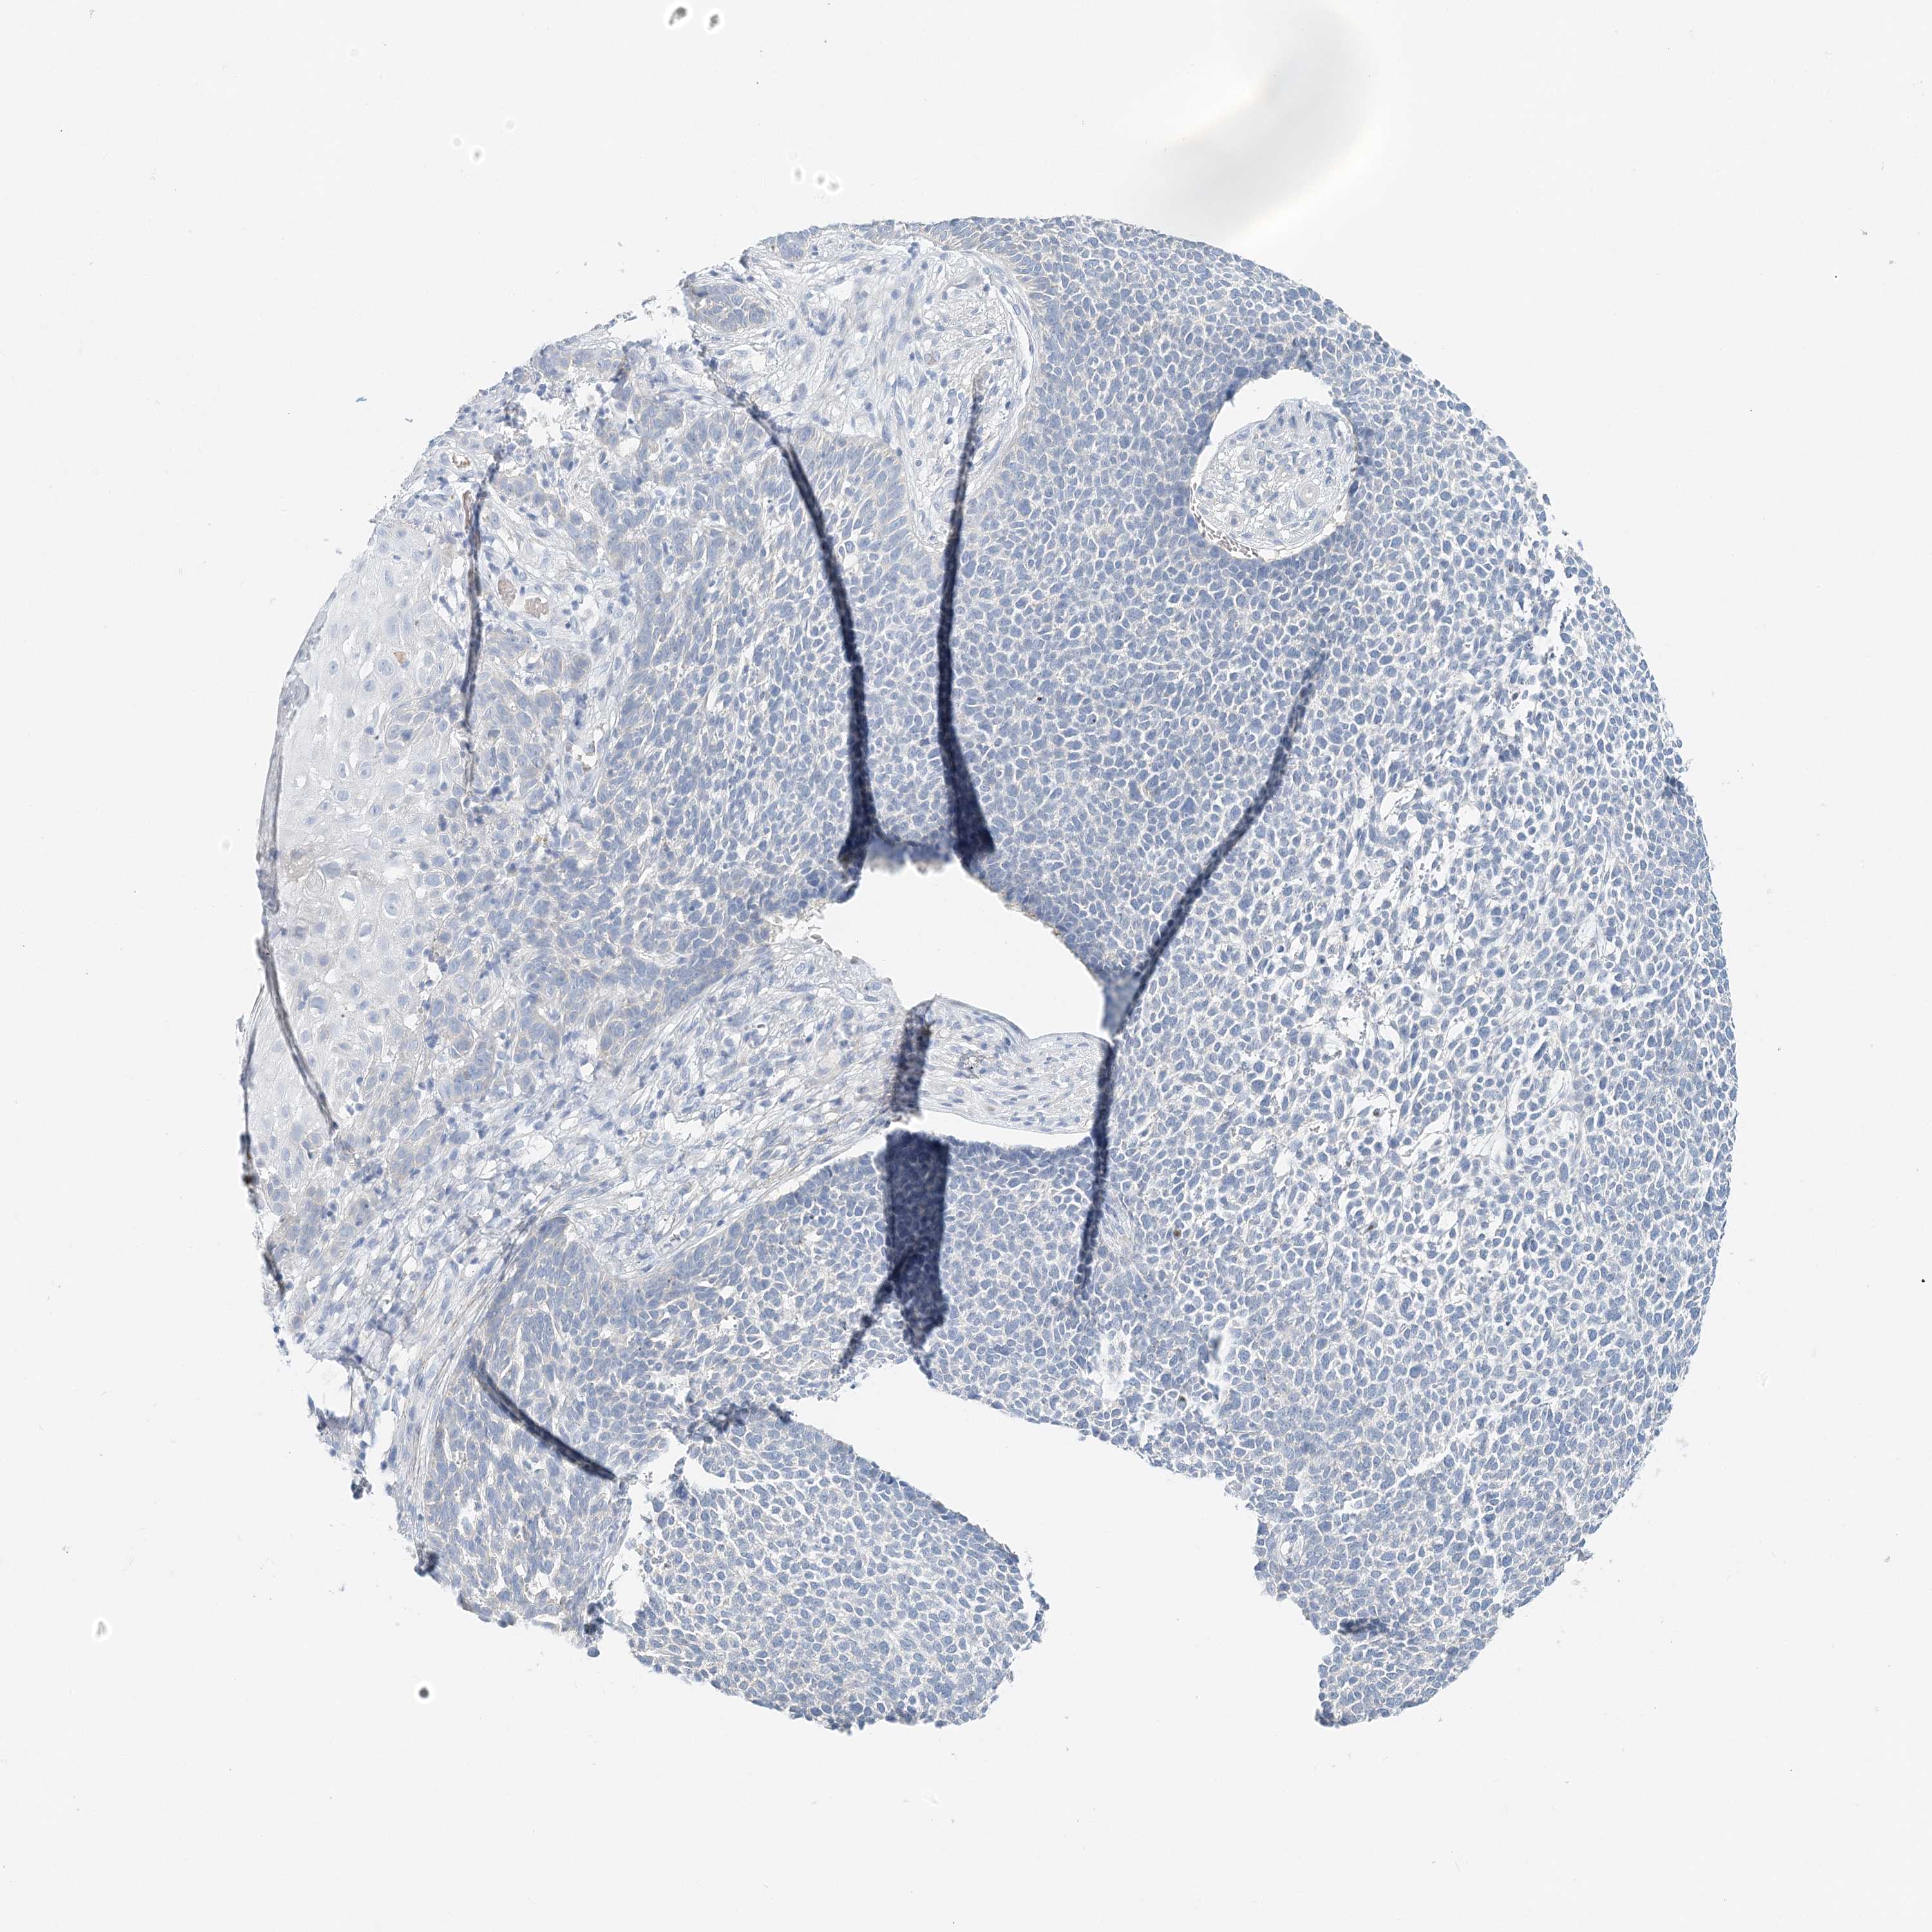

SKIN CANCER - Protein expressioni

A mouse-over function shows sample information and annotation data. Click on an image to view it in a full screen mode. Samples can be filtered based on level of antibody staining by selecting one or several of the following categories: high, medium, low and not detected. The assay and annotation is described here.

Each image is clickable and will lead to virtual microscopy that enables deeper exploration of all samples and also displays staining intensity scores, fraction scores and subcellular localization as well as patient and tissue information for each sample.

Antibody HPA035675

Staining

High

Medium

Low

Not detected

Intensity

Strong

Moderate

Weak

Negative

Quantity

>75%

75%-25%

<25%

None

Location

Nuclear

Cytoplasmic/membranous

Cytoplasmic/membranous,nuclear

Basal cell carcinoma

Squamous cell carcinoma, NOS

Squamous cell carcinoma, metastatic, NOS